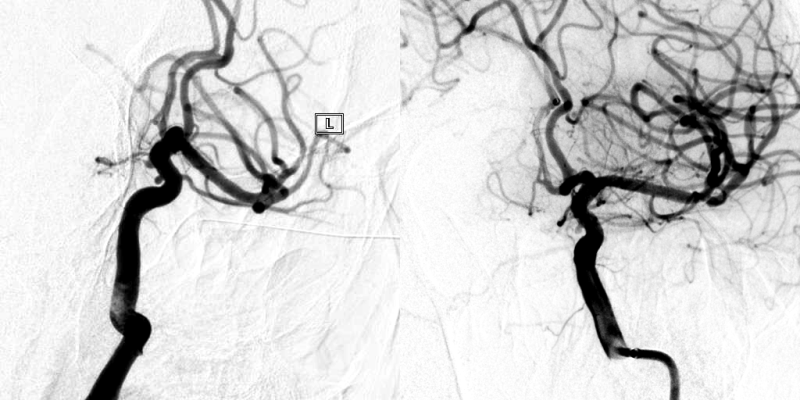

温柔守候——当烟雾病遇上宽颈动脉瘤

患者基本信息女性,51岁,主诉头痛1天入院治疗。初步诊断1、烟雾病;2、动脉瘤破裂蛛网膜下腔出血;3、胚胎型大脑后动脉动脉瘤术前影像学检查动脉瘤位置、侧别:右侧大脑后动脉P1段测量大小:5.93mm×7.04mm×6.44mm瘤颈测量:4.50mm子瘤大小:2.44mm×2.38mm×2.07mm 此病例动脉瘤瘤颈宽,母动脉瘤体顶端有一个子瘤,顶端血流导入子瘤,造成子瘤破裂出血风险高。 术前思考1、该动脉瘤位于右侧大脑后动脉P1段,且患者系烟雾病,大...